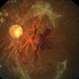

- Dengue Fever, rosacea conjunctivitis, preretinal hemorrhage

- Imaging device

- Fundus camera

- Fundus photograph of the left eye of a 32-year-old gentleman with dengue fever and thrombocytopenia. Photograph shows extensive retinal and pre-retinal haemorrhages, roth spots but no dengue retinitis. Same patient as in images 1-5.